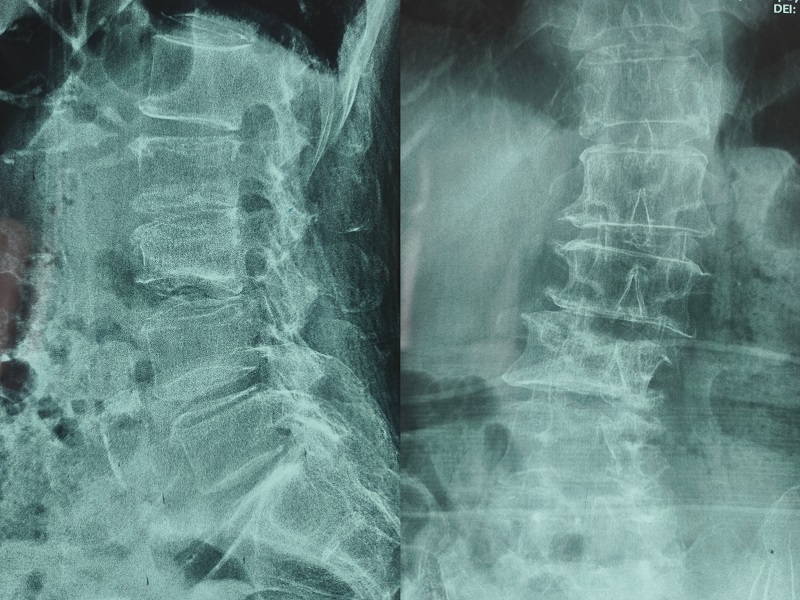

術后圖像